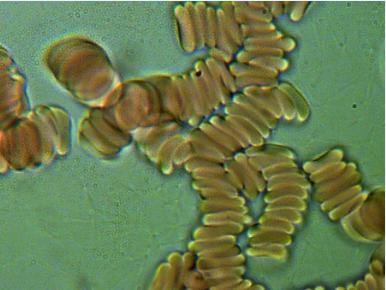

1.RULONIZACJA I AGREGACJA ERYTROCYTÓW

To poważne zagrożenie zatorowo - zakrzepowe, co klinicznie może spowodować zapalenie naczyń obwodowych, zawał serca, udar mózgu a nawet nagły zgon. Agregacji i rulonizacji nie można stwierdzić tradycyjnymi badaniami diagnostycznymi.